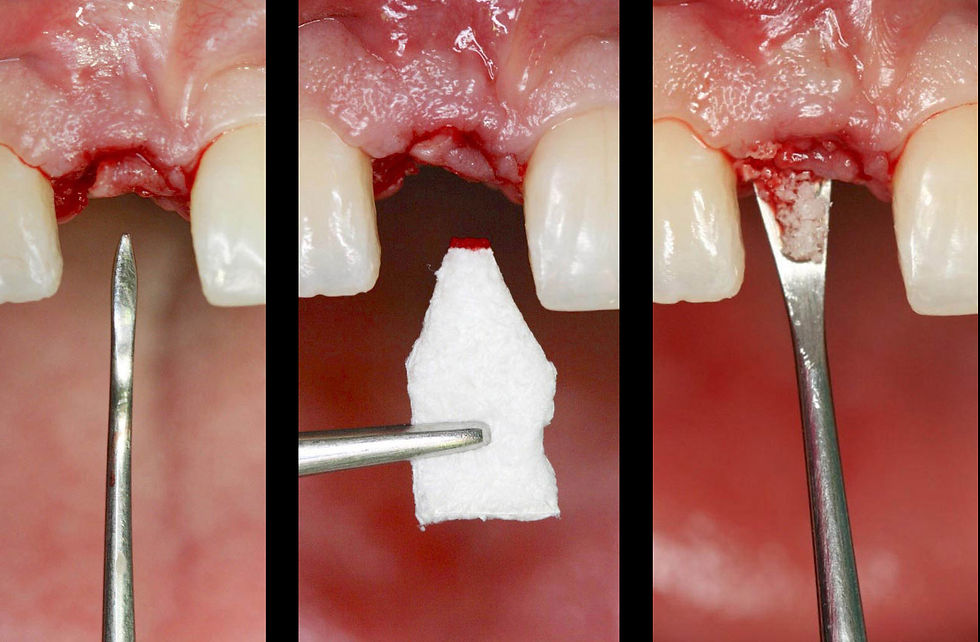

Socket preservation. The tissue graft collected from the palate is positioned to protect the biomaterial inserted in the alveolus.